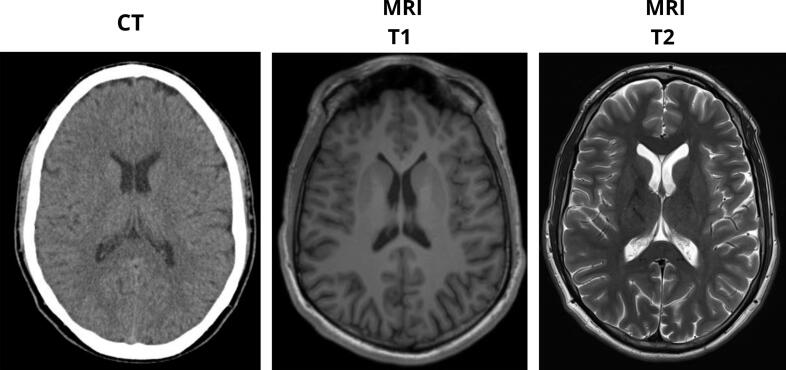

Regarding neurological assessment, continuous video electroencephalography (EEG) monitoring showed no epileptiform activity. Both contrast-enhanced computed tomography (CT) and magnetic resonance imaging (MRI) of the brain were normal (Fig. 2). A normal electrocardiogram was reported. Additional laboratory analyses showed a normal CRP level and a total CK value of 360 U/L.